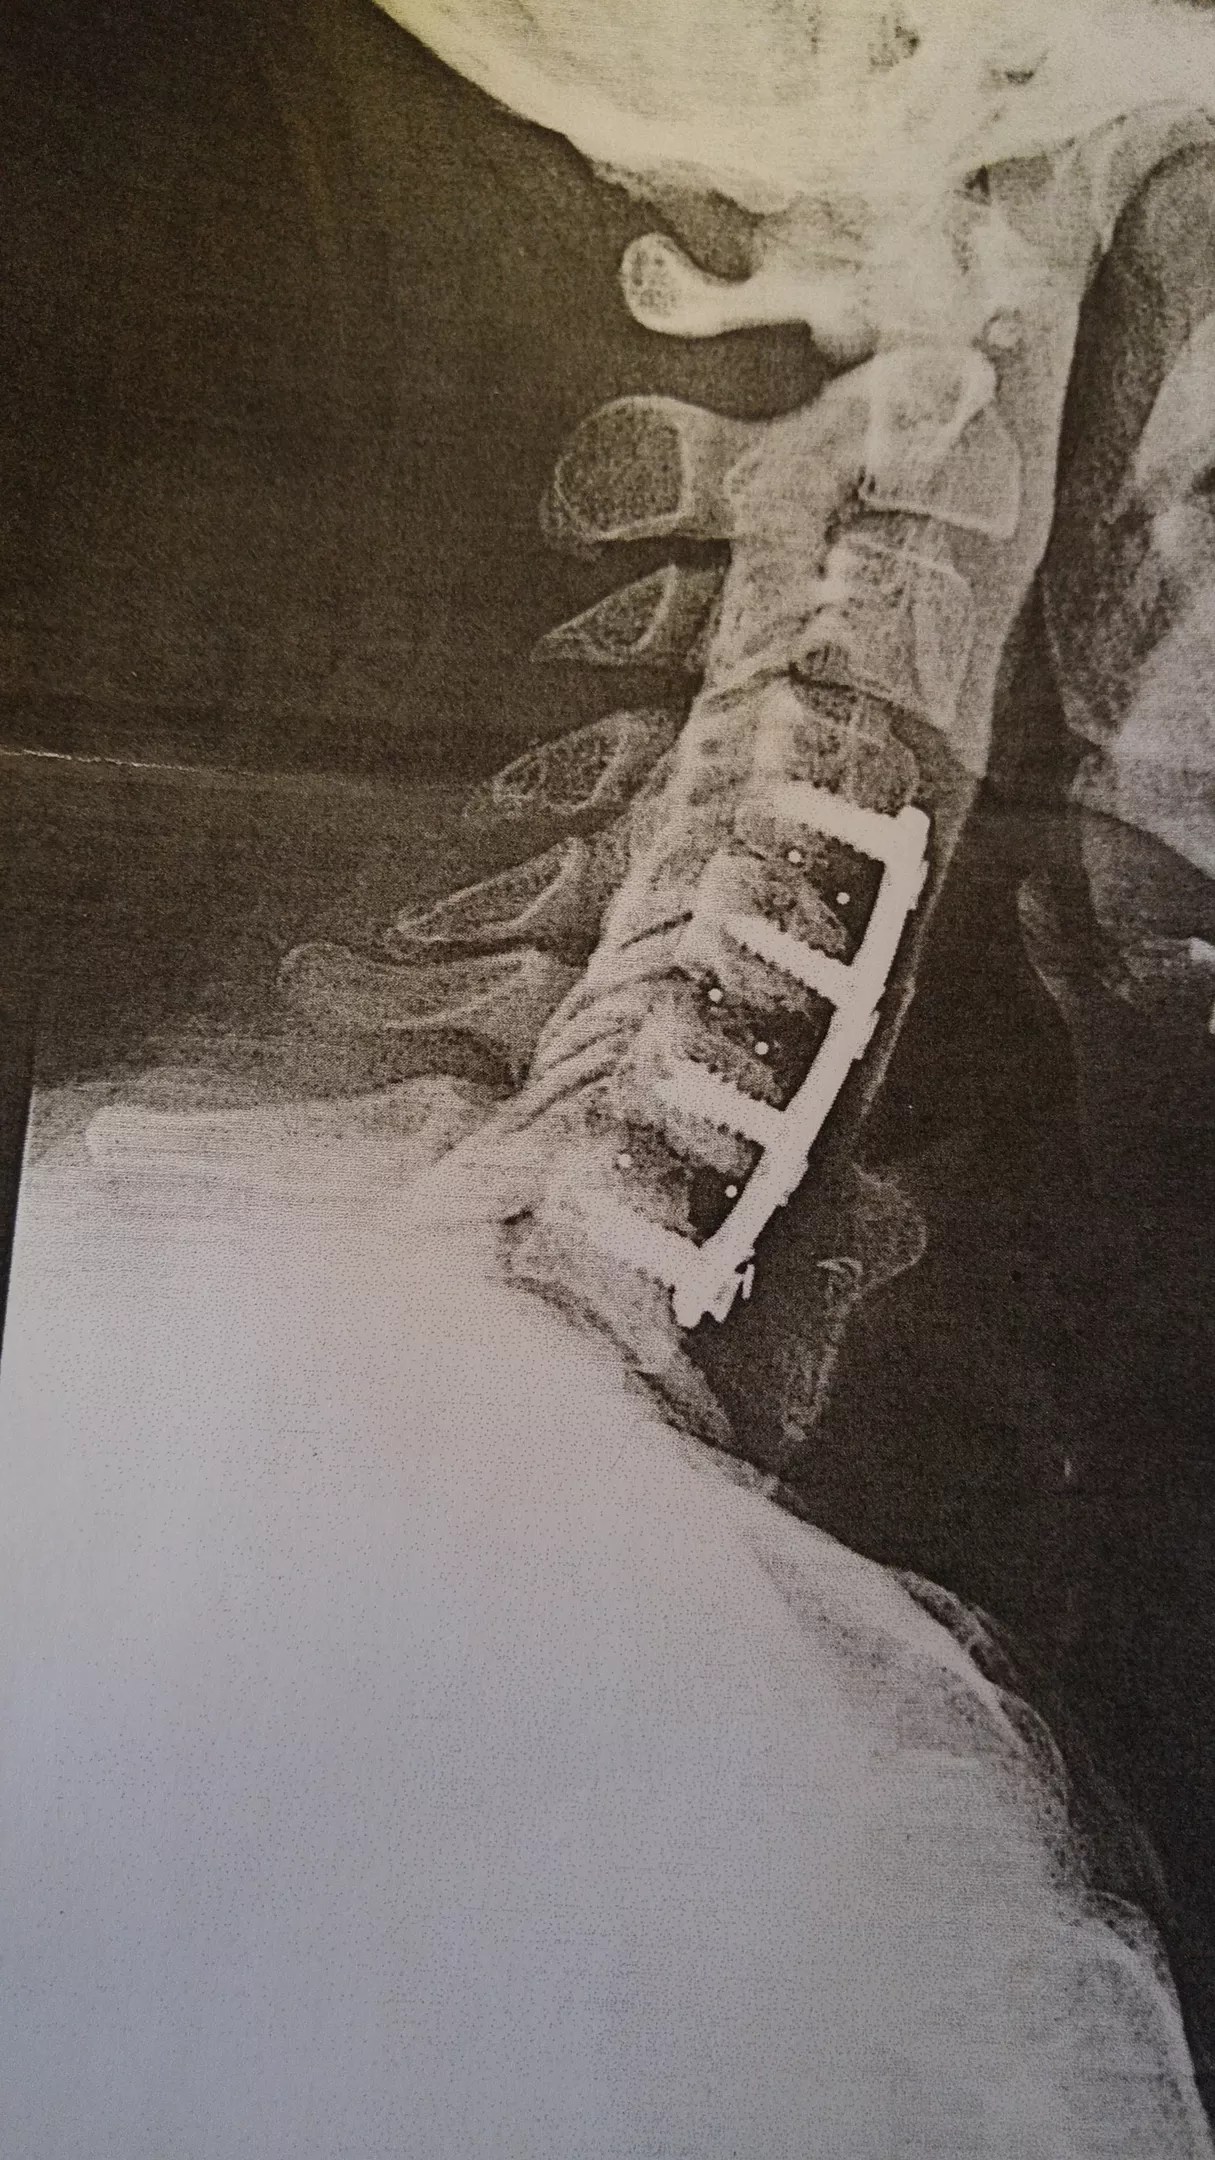

Garrett’s X-ray after his first surgery, which he says the surgeon botched.

The simple procedure consisted of taking some cadaver bone, sticking it between four of his vertebrae and fusing it all together using steel rods and screws. Garrett says the surgeon used the wrong kind of bone and didn’t tighten the screws, causing one of them to work its way out and nearly impale his trachea.

“They tell you that it’s a quick fix, and then you have the surgery and learn differently. ‘You had four vertebrae fused together. You got steel rods and screws in your neck. You’re never going to be the same as you were before. You’re never going to be the same again,'” he recalled the surgeon telling him.